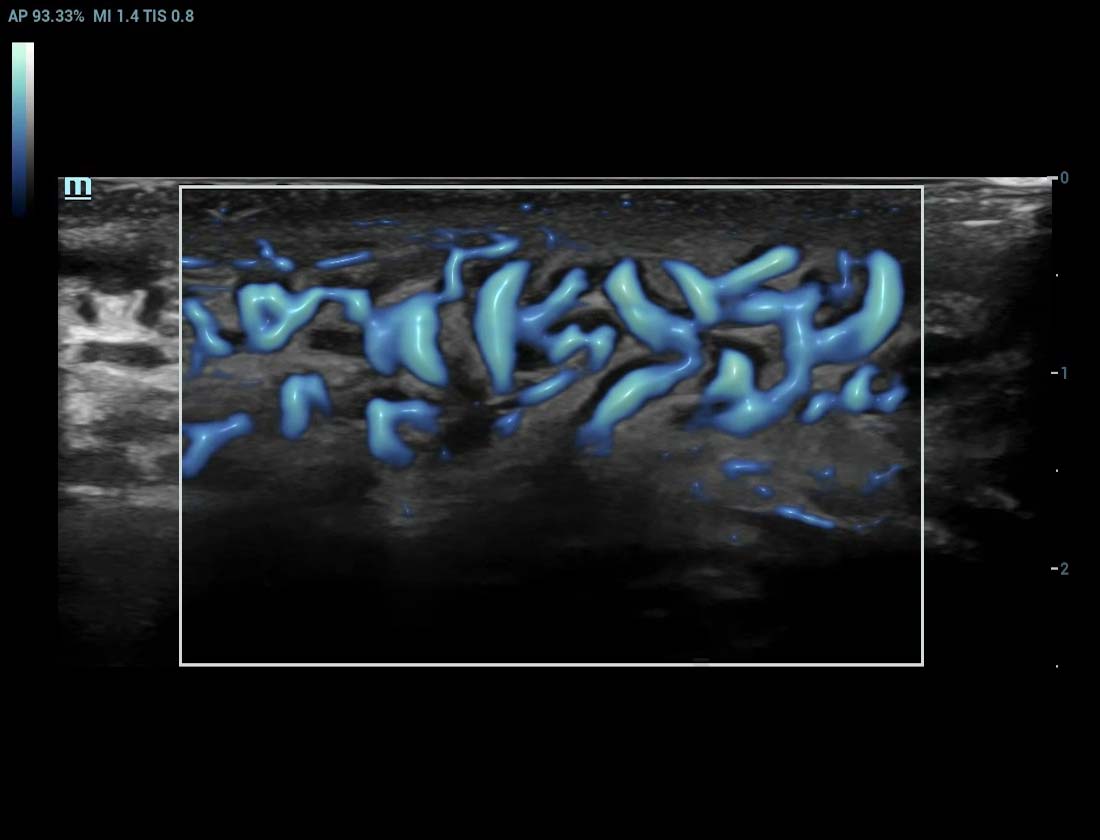

Glazing Flow varicocele

Ultra Micro Angiography (UMA)

UMA migliora la sicurezza diagnostica ampliando la visibilitĂ dei flussi sanguigni fino al livello dei vasi piĂč piccoli, con una sensibilitĂ e una risoluzione superiori.

Glazing Flow varicocele sUMA